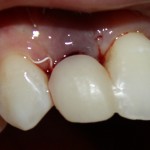

И удалили. Вместе с протезом. Через 15 минут после удаления Давид зафиксировал временный протез с опорой на импланты:

Уточню — это ВРЕМЕННЫЙ протез. При тотальном протезировании на имплантах, это почти необходимая вещь. Ибо заново настроить зубочелюстную систему, где вообще не осталось зубов, не так просто, как кажется. На это требуется время и ряд коррекций. К тому же, временный протез позволяет определить, как «работают» импланты под нагрузкой.